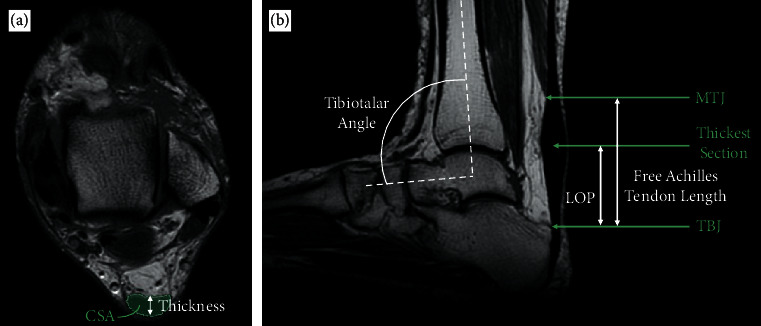

Objectives: The free Achilles tendon is defined as the region of tendon distal to the soleus which is "unbuttressed," i.e., unsupported by muscular tissue. We reasoned that a relative lack of distal buttressing could place the tendon at a greater risk for developing Achilles tendinopathy. Therefore, our primary goal was to compare the free Achilles tendon length between those with midportion or insertional Achilles tendinopathy and healthy controls.

Design: This is a retrospective case-control study. Setting. Hospital in Vancouver, Canada. Participants. 66 cases with Achilles tendinopathy (25 insertional, 41 midportion) consecutively drawn from a hospital database within a 5-year period and matched to 66 controls (without tendinopathy) based on sex, age, and weight. Main outcome measures. Odds ratio of the risk of developing Achilles tendinopathy given the length of free tendon, defined anatomically on MRI, after adjustment for confounders.

Results: MRI-defined free Achilles tendon length is a statistically significant predictor of having midportion Achilles tendinopathy (odds ratio = 0.53, 95% confidence interval 1.13 to 2.07). Midportion Achilles tendinopathy cases had significantly longer free tendons (Mdn = 51.2 mm, IQR = 26.9 mm) compared to controls (Mdn = 40.8 mm, IQR = 20.0 mm), p = 0.007. However, there was no significant difference between the free Achilles tendon lengths in insertional AT cases (Mdn = 47.9 mm, IQR = 15.1 mm) and controls (Mdn = 39.2 mm, IQR = 17.9 mm), p = 0.158. Free Achilles tendon length was also correlated with the tendon thickness among those with Achilles tendinopathy, rτ = 0.25, and p = 0.003.

Conclusions: The MRI-defined length of the free Achilles tendon is positively associated with the risk of midportion Achilles tendinopathy. A relative lack of distal muscular buttressing of the Achilles tendon may therefore influence the development of tendinopathy.